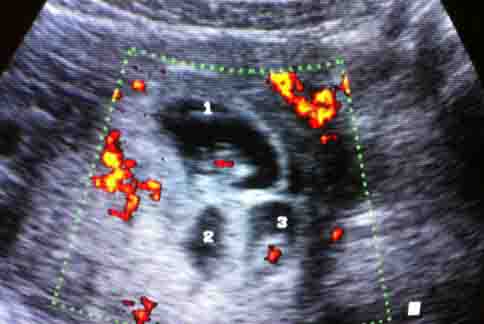

透過第三代試管嬰兒(PGD)胚胎著床前基因晶片診斷,並篩檢出沒有CMT疾病的胚胎,婦人成功懷有三胞胎健康寶寶。(圖片提供/蔡鋒博醫師)透過第三代試管嬰兒(PGD)胚胎著床前基因晶片診斷,並篩檢出沒有CMT疾病的胚胎,婦人成功懷有三胞胎健康寶寶。(圖片提供/蔡鋒博醫師)

婦產科醫師蔡鋒博表示,婦人為了求子卻又擔心孩子也會遺傳先生的小腿腓骨肌萎縮症,於是為婦人進行胚胎著床前基因晶片診斷試管嬰兒(PGD),並做胚胎切片,再由彰化基督教醫院基因醫學部陳明主任用基因晶片篩檢出沒有CMT疾病的胚胎,於是根據陳明主任的基因晶片的書面報告,植入 健康未帶病的胚胎到婦人子宮,目前已經看到3個胚囊(即三胞胎,都有正常心跳),目前胚胎已經8週大。